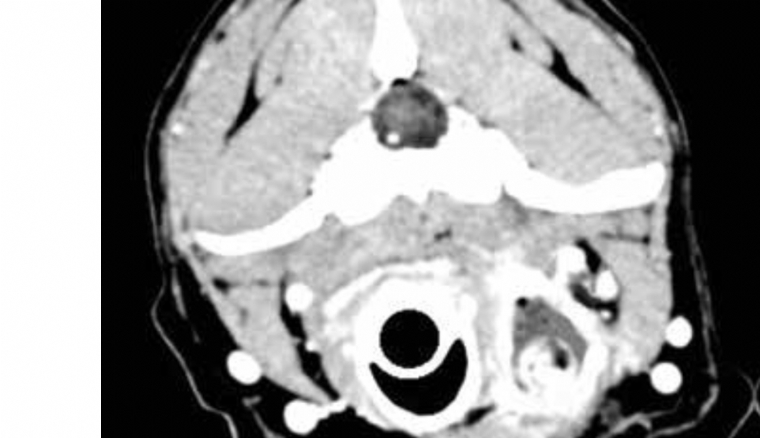

Mercredi 7 Septembre 2022 Animaux de compagnie 44846Photo n° 1A : Coupe axiale caudalement au larynx (1A) et coupe sagittale de la tête et du cou (1B).

Un examen tomodensitométrique de la tête et du cou est proposé pour réaliser un bilan d'extension de cette masse (photos).

Le scanner confirme la présence d'un corps étranger à l'origine de la masse : les images (photos) révèlent la présence d'un bâton de 12 cm de longueur sur 7 mm de diamètre s'étendant de la base de la langue jusqu'au larynx, positionné à gauche de ce dernier.

Le bâton est entouré d'une capsule hyperdense, rehaussée par l'injection du produit de contraste et d'un contenu liquidien hypodense.

Le larynx et l'oesophage semblent intacts.